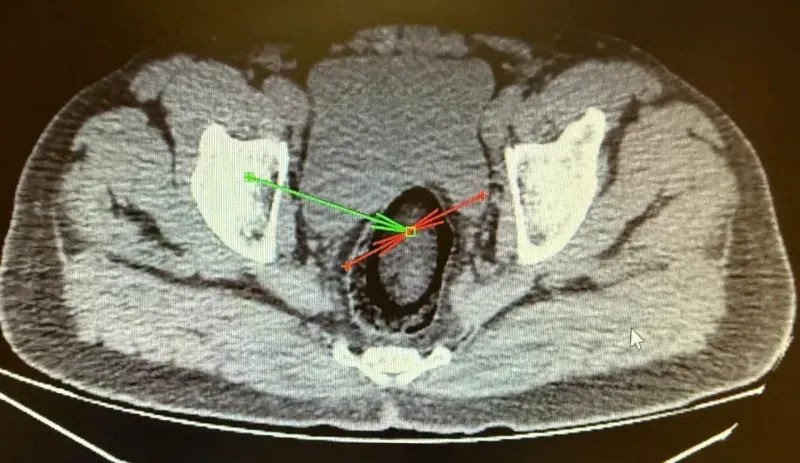

Kars Emniyet Müdürlüğü Narkotik Suçlarla Mücadele Şube Müdürlüğü ekipleri, Digor-Kars kara yolunda yaptığı uygulamada, yolcu otobüsünde arama yaptı. Polis, hareketlerinden şüphelendiği F.H.'yi gözaltına aldı. Kars Harakani Devlet Hastanesi'ne götürülen F.H.'nin çekilen röntgeninde, makatında uyuşturucu tespit edildi. 105,98 gram metamfetamin, cerrahi operasyonla çıkarıldı. Emniyetteki işlemlerinin ardından adliyeye sevk edilen şüpheli, çıkarıldığı hakimlik tarafından tutuklandı.